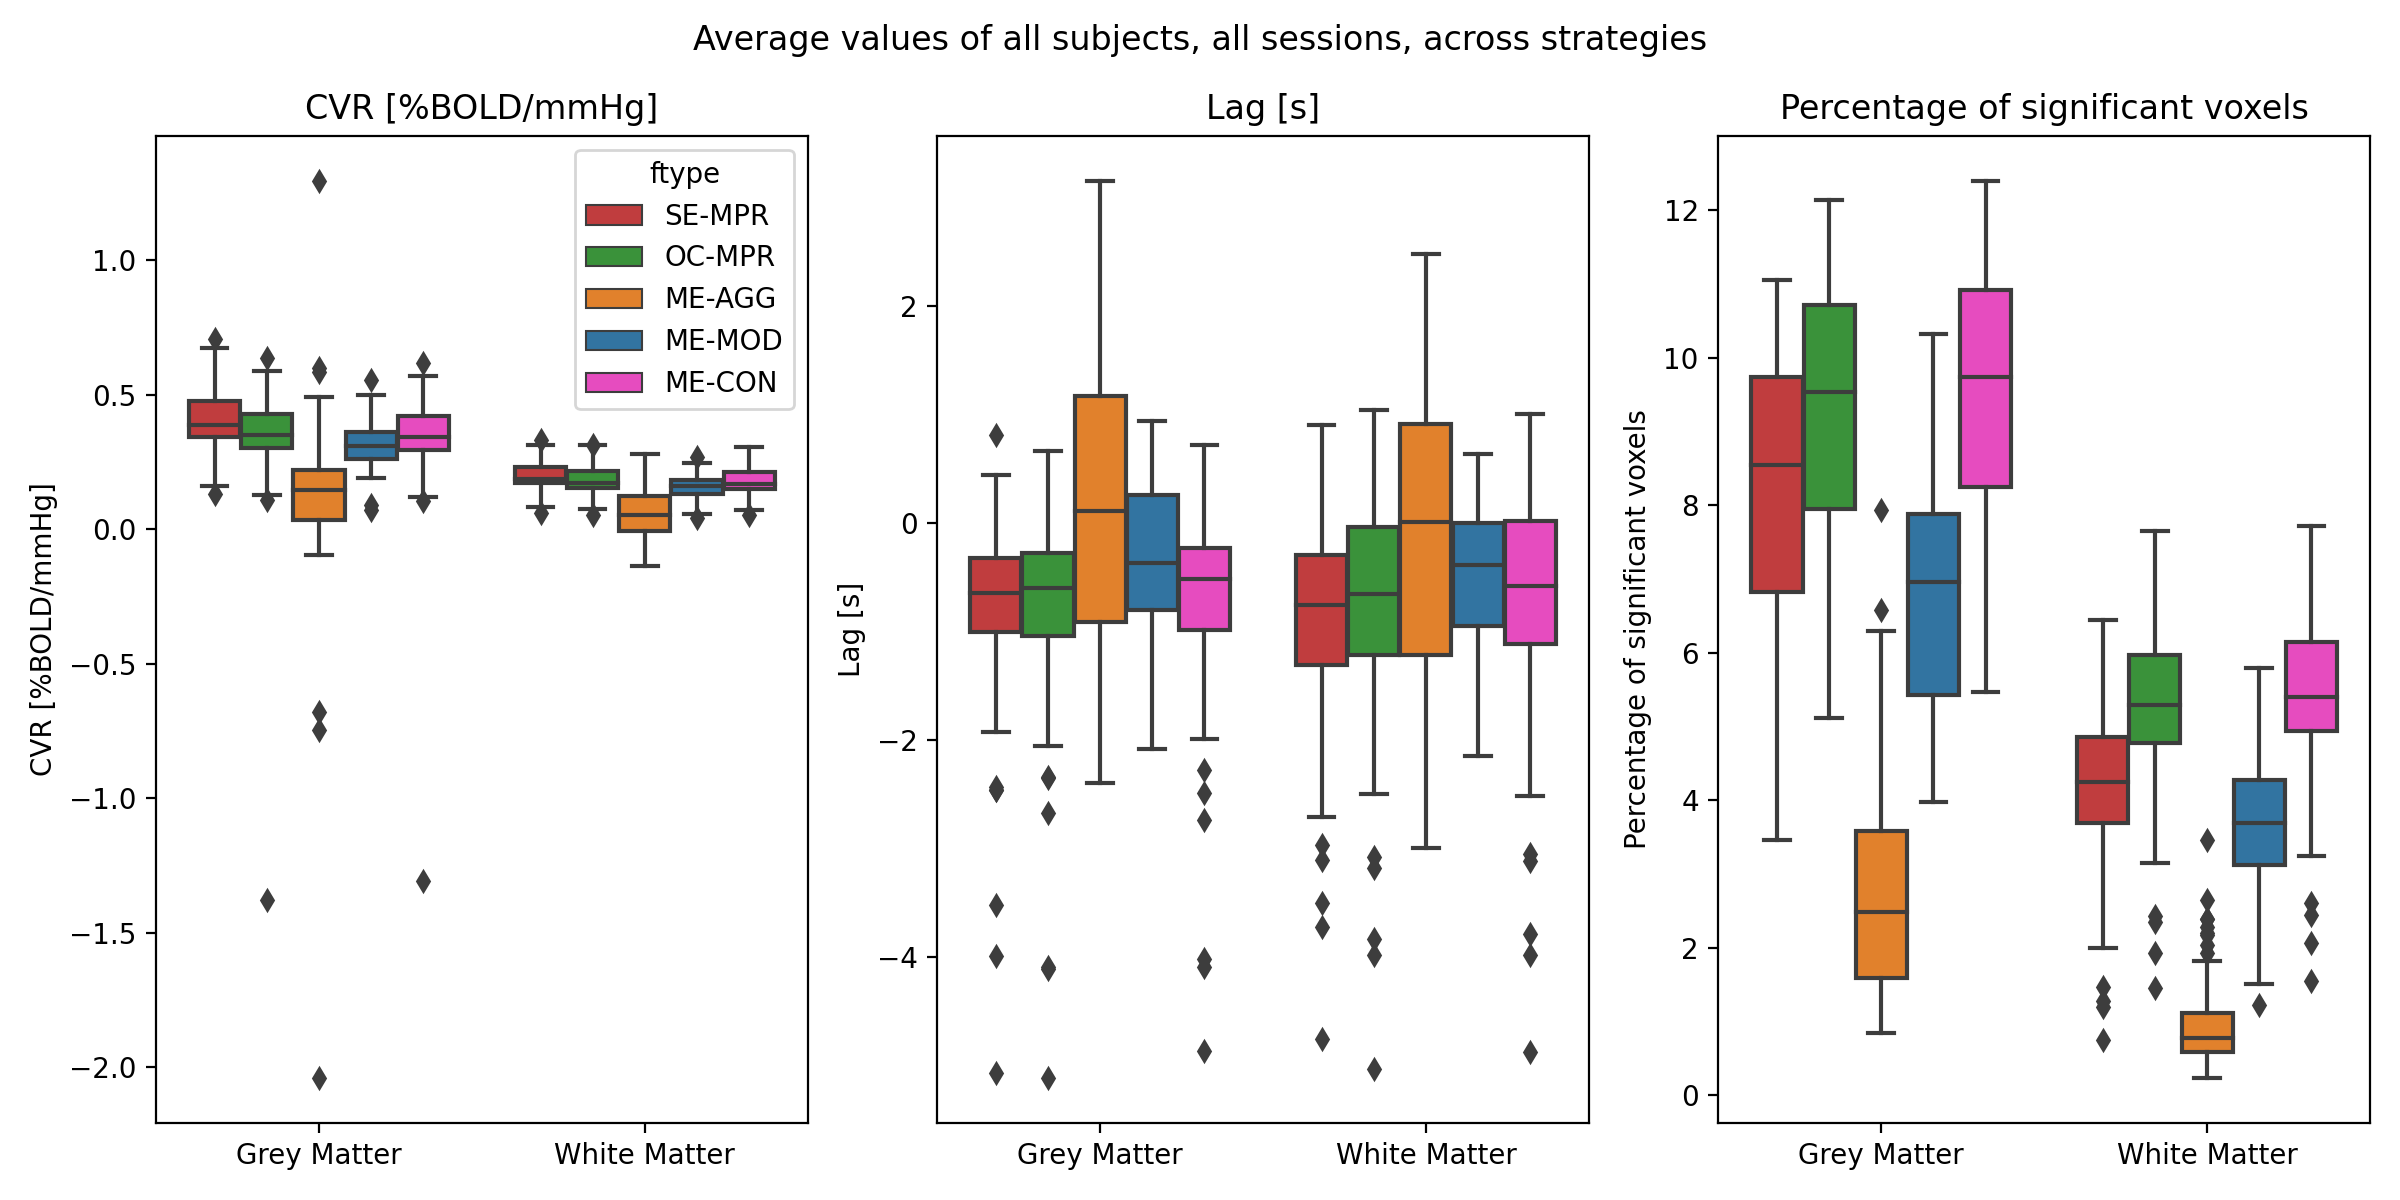

Methods: ME-ICA based denoise

- their effect in terms of making signal (DVARS) independent of motion (FD) [LME]: $$DVARS_t = \sqrt{\lang [I_t(x) - I_{t-1}(x)]^2}$$ $$FD_t=|\Delta d_x|+|\Delta d_y|+|\Delta d_z|+|\Delta \alpha |+|\Delta \beta|+|\Delta \gamma |$$

$$DVARS\sim FD\ast model+(1|subject)+(1|session)$$

- the resulting CVR and lag maps spatially [LME]: $$X\sim model+(1|subject)+(1|session)$$

- the resulting CVR and lag maps' reliability [ICC]: $$X \sim (1|subject)+(1|session)$$

We compared:

Results: model comparison

Moia et al. 2021 (NeuroImage)

CVR amplitude

CVR lag

CVR amplitude

CVR lag

Results: model comparison

Moia et al. 2021 (NeuroImage)

CVR amplitude

CVR lag

CVR amplitude

CVR lag

Reliability [ICC (2,1)]

Moia et al. 2021 (NeuroImage)

OC-MPR vs ME-CON

ME-CON should be better than OC-MPR in temporal-dependent application

Conclusion

In data characterised by global responses and high motion collinearity, such as CVR, a conservative ICA-based approach best removes motion-related effects, while obtaining reliable responses, but a simple optimal combination of ME data provides similar estimations

However, further examinations are required to translate these observations to paradigms with lower collinear motion and more focal responses (e.g. functional task), or in which there is no task information available (e.g. rest)

An ICA-based conservative denoising improves BH-induced CVR mapping, but a simpler optimal combination of ME data could be already sufficient.